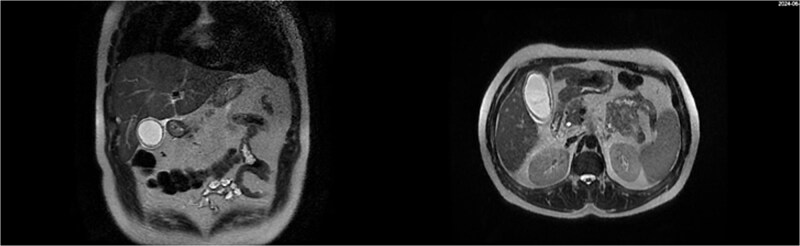

Abstract Image